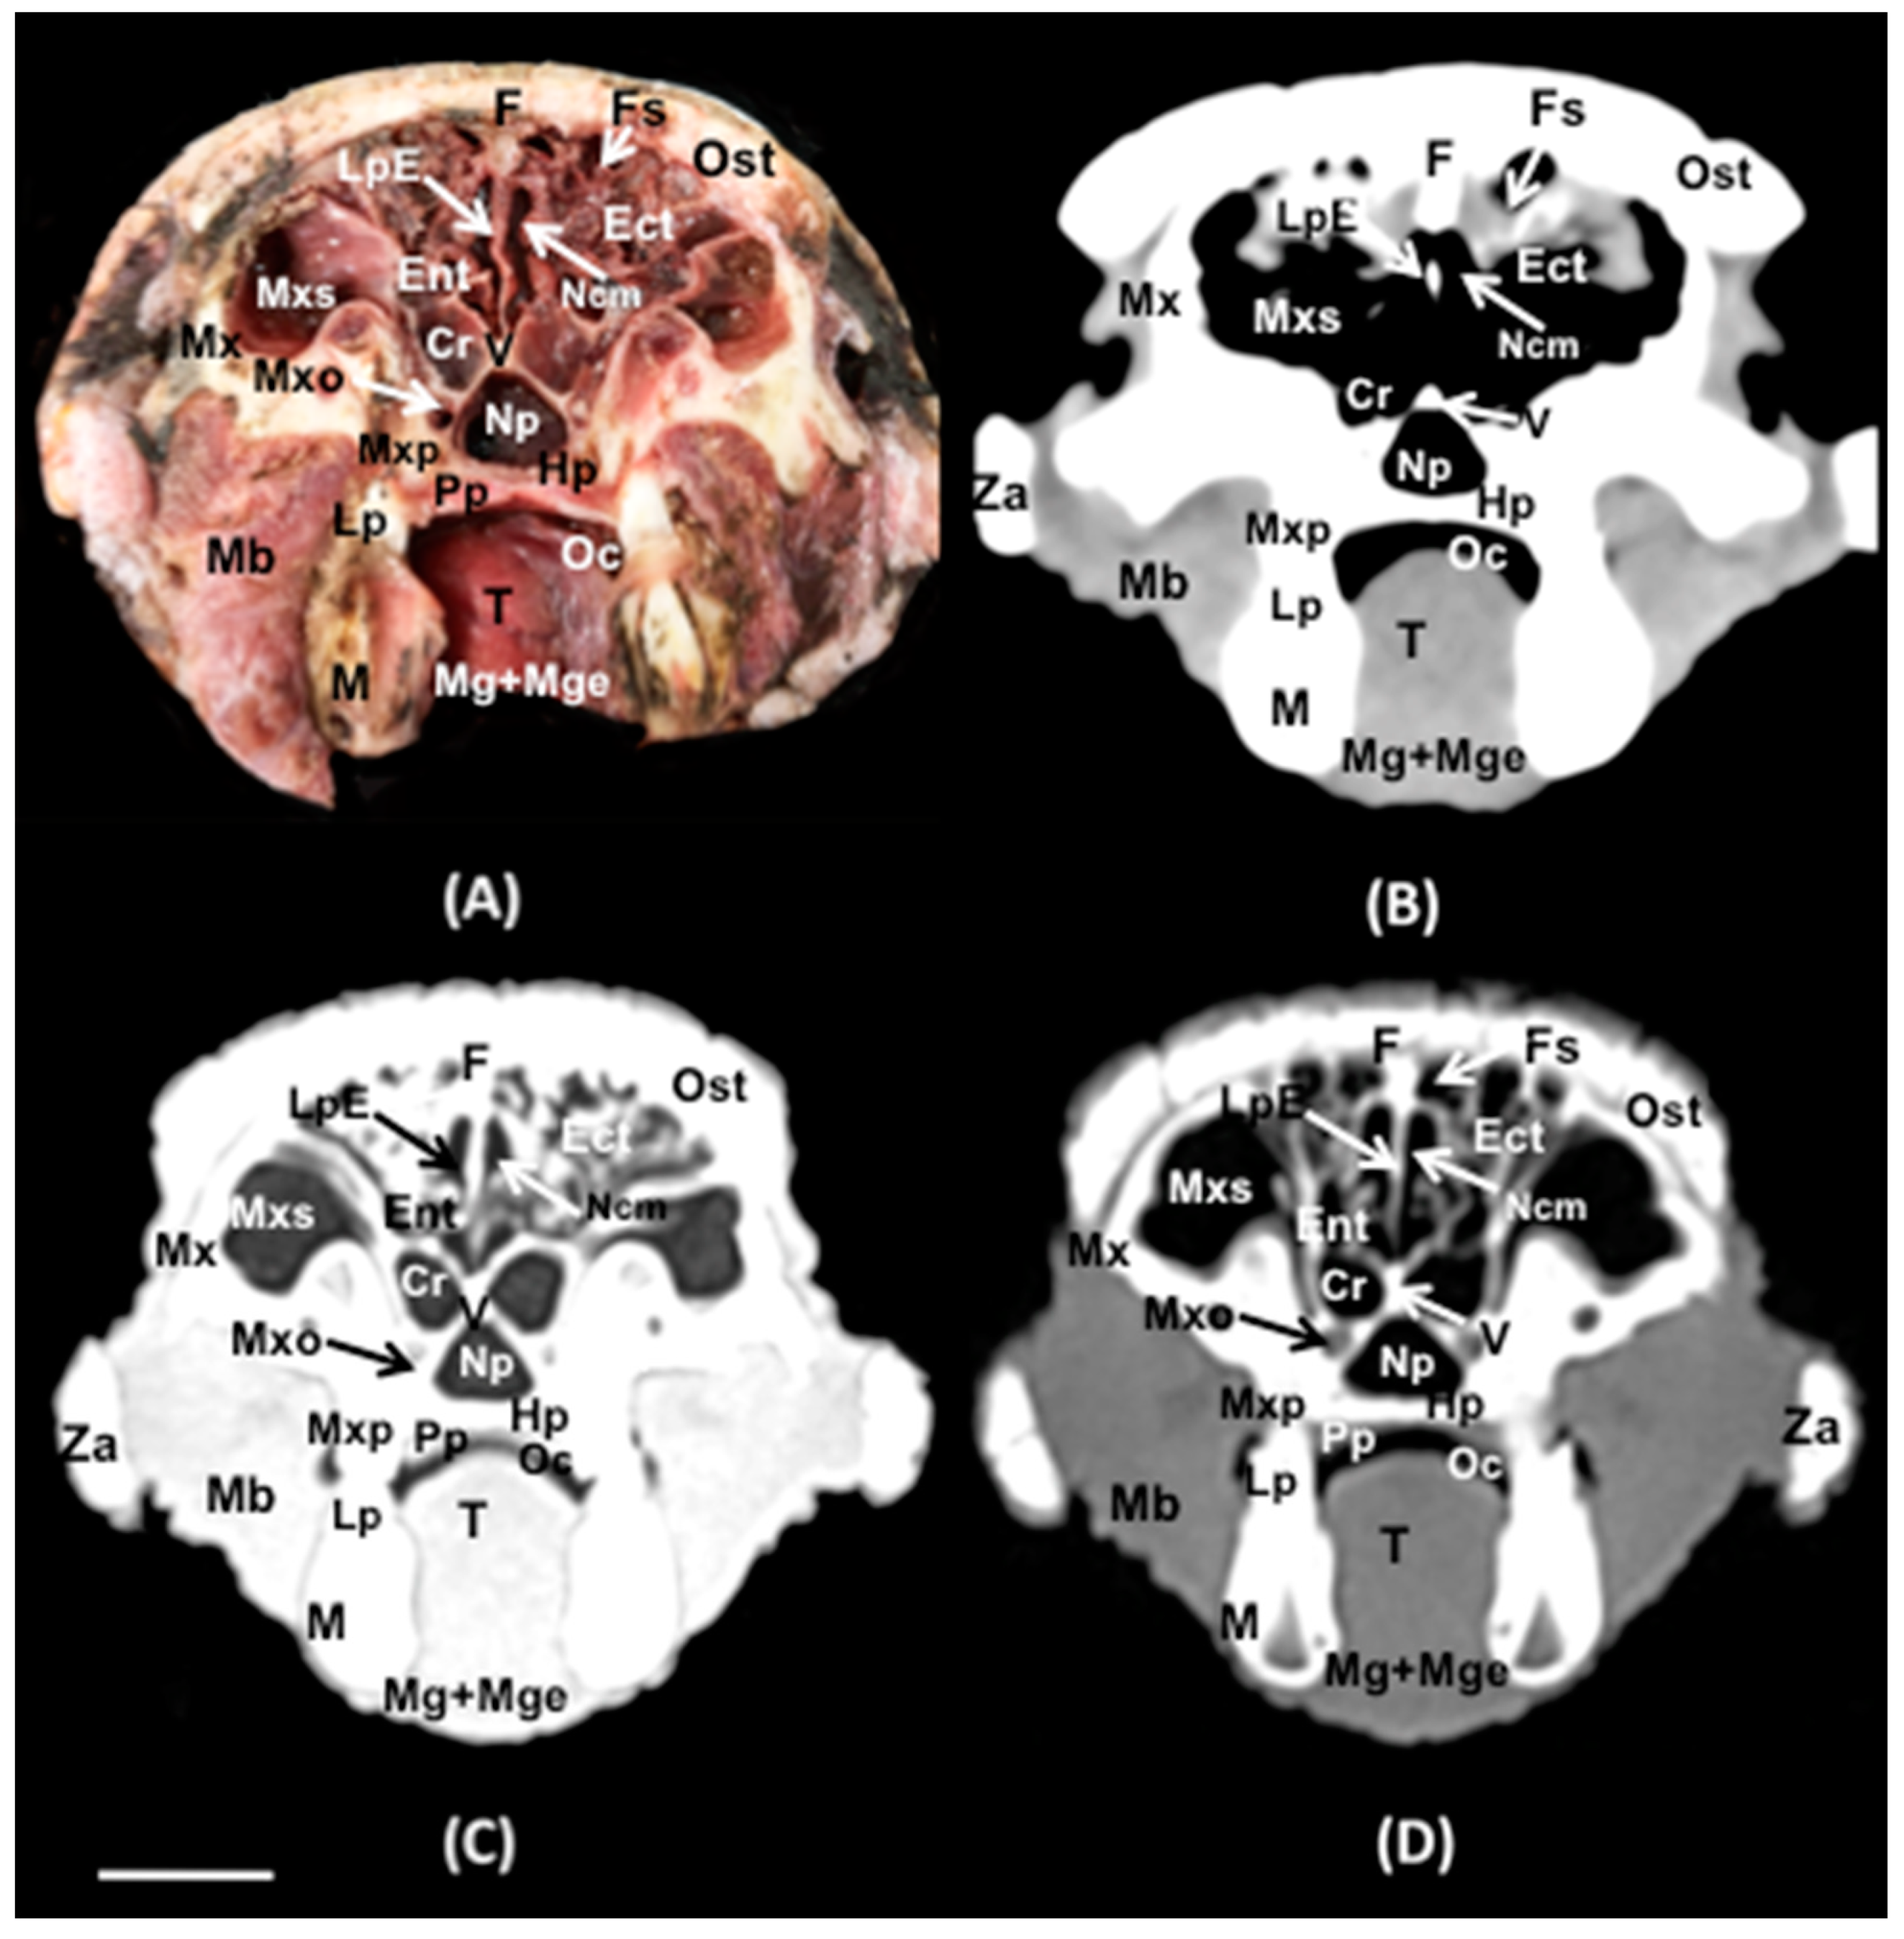

3.1. Anatomical Sections

3.2. Computed Tomography (CT)